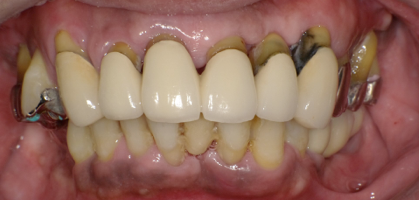

術後の写真です。フレアーアウトした分、歯を引っ込めてかみ合わせも若干高くしています。

術前の口元と別人になっているのが分かると思います。

オールオンフォーの良いところはこのように好きなように歯を並べることができることです。

欠点は清掃が難しいこと、ネジ式なのでネジの穴の部分に仮の蓋をつけないといけないので少し審美が劣るところです。